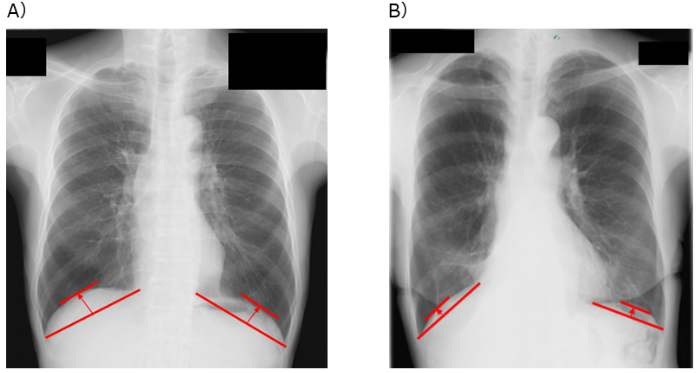

A)胸部X線画像による、横隔膜ドーム高の測定方法、B)横隔膜ドーム高が低い患者の例

そこで研究グループは、胸部X線画像から簡便に測定できる横隔膜の位置の高さである「横隔膜ドーム高※3」という指標に注目しました。横隔膜ドーム高は、肺機能や運動耐容能と密接に関連することが明らかになっており、より簡便かつ患者に負担なく術後予後を予測する指標となる可能性があります。しかし、これまで肺がん患者において、横隔膜ドーム高と術後の予後との関連性は明らかにされていませんでした。

研究グループは、近畿大学病院において肺がんの肺葉切除術を受けた患者を対象に、術前1カ月以内に撮影された胸部X線画像を用い、肺腫瘍側の横隔膜ドーム高を測定しました。その結果、多変量解析※5 において、術前の横隔膜ドーム高は術後予後に影響を及ぼすことが知られている喫煙状況、肺機能、がんのステージなどの因子の影響を受けず、独立した術後予後を予測できる因子であることが明らかとなりました(HR=2.10、p<0.01)。さらに、時間経過に伴う生存率の推移を示すカプラン・マイヤー生存曲線※6 による解析では、横隔膜ドーム高が低い患者群において、3年間の全生存率※7 が有意に低く(p<0.01)、加えて肺炎や呼吸不全などの呼吸器疾患による死亡に限定した場合でも、3年の疾患特異的生存率※8 が有意に低いことが示されました(p<0.01)。これらの結果から、横隔膜ドーム高が低い患者群に対する術前呼吸リハビリテーションは、術後予後改善へ向けて重要である可能性が示唆されました。

※3 横隔膜ドーム高:横隔膜がどれくらい上に持ち上がっているか(高さ)を示す指標。